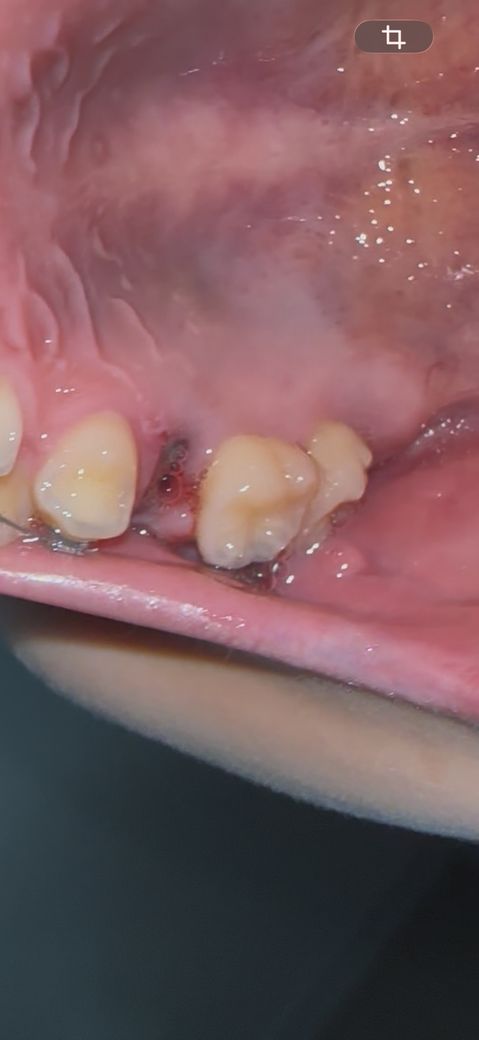

발치 후 혈병 상태 괜찮은지 질문드립니다

1월 6일날 발치했고 잘 아물어가는지 궁금해요

• 1번 째 사진

사진상 발치부위는 육아,염증조직이 잘 자리를 잡았고 치유도 양호한 편이니 걱정 안하셔도 됩니다